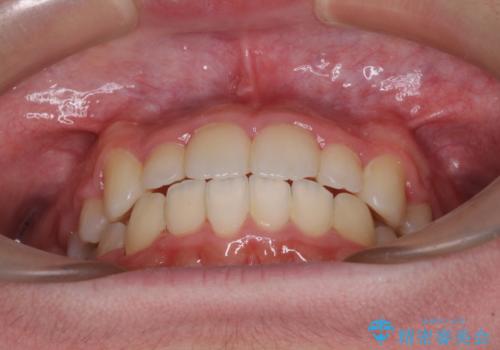

叢生のため磨き残しの多い歯列でしたが、1年弱で治療を終了でき、磨き残しや歯肉の腫れが著しく改善されました。